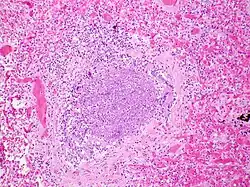

Acute inflammatory exudate occluding the lumen of the bronchiole and acute inflammation of part of the wall of the bronchiole

Histology Slide - Acute inflammatory exudate occluding the lumen of the bronchiole and acute inflammation of part of the wall of the bronchiole. It shows at the cellular level the inflammation that occurs in the bronchiole of a child with bronchiolitis.